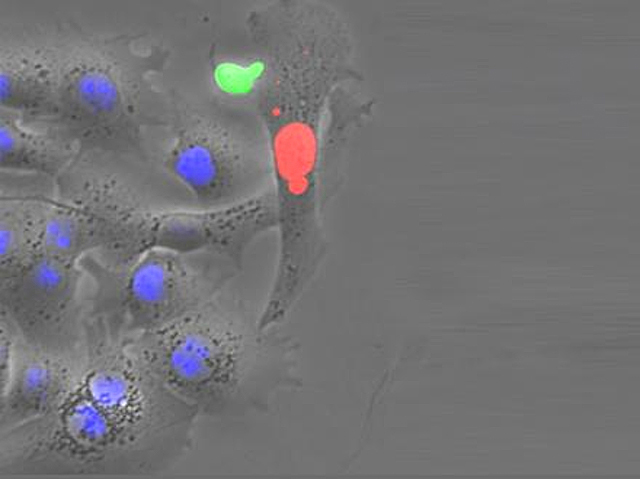

Although infection with the hepatitis B virus (HBV), which can cause severe liver disease and even cancer, is preventable with a vaccination, it's estimated that more than 260 million people worldwide are chronically infected. And, for such individuals there's currently no cure. That may be set to change however, if the results of a recent mouse experiment hold true in humans. Humanized mice – containing HBV-infected human liver cells – have been treated with a combination of an antiviral drug and human T cells engineered to express specific anti-HBV receptors. The tooled-up T cells have increased power for killing HBV-infected cells. Indeed, such a T-cell (in green) is shown here attacking a cell expressing HBV proteins (red), while uninfected cells (blue) remain unharmed. Importantly, this approach successfully cleared the mice of their infection, providing hope that such T-cells may also eliminate the disease and associated cancer risk in patients.